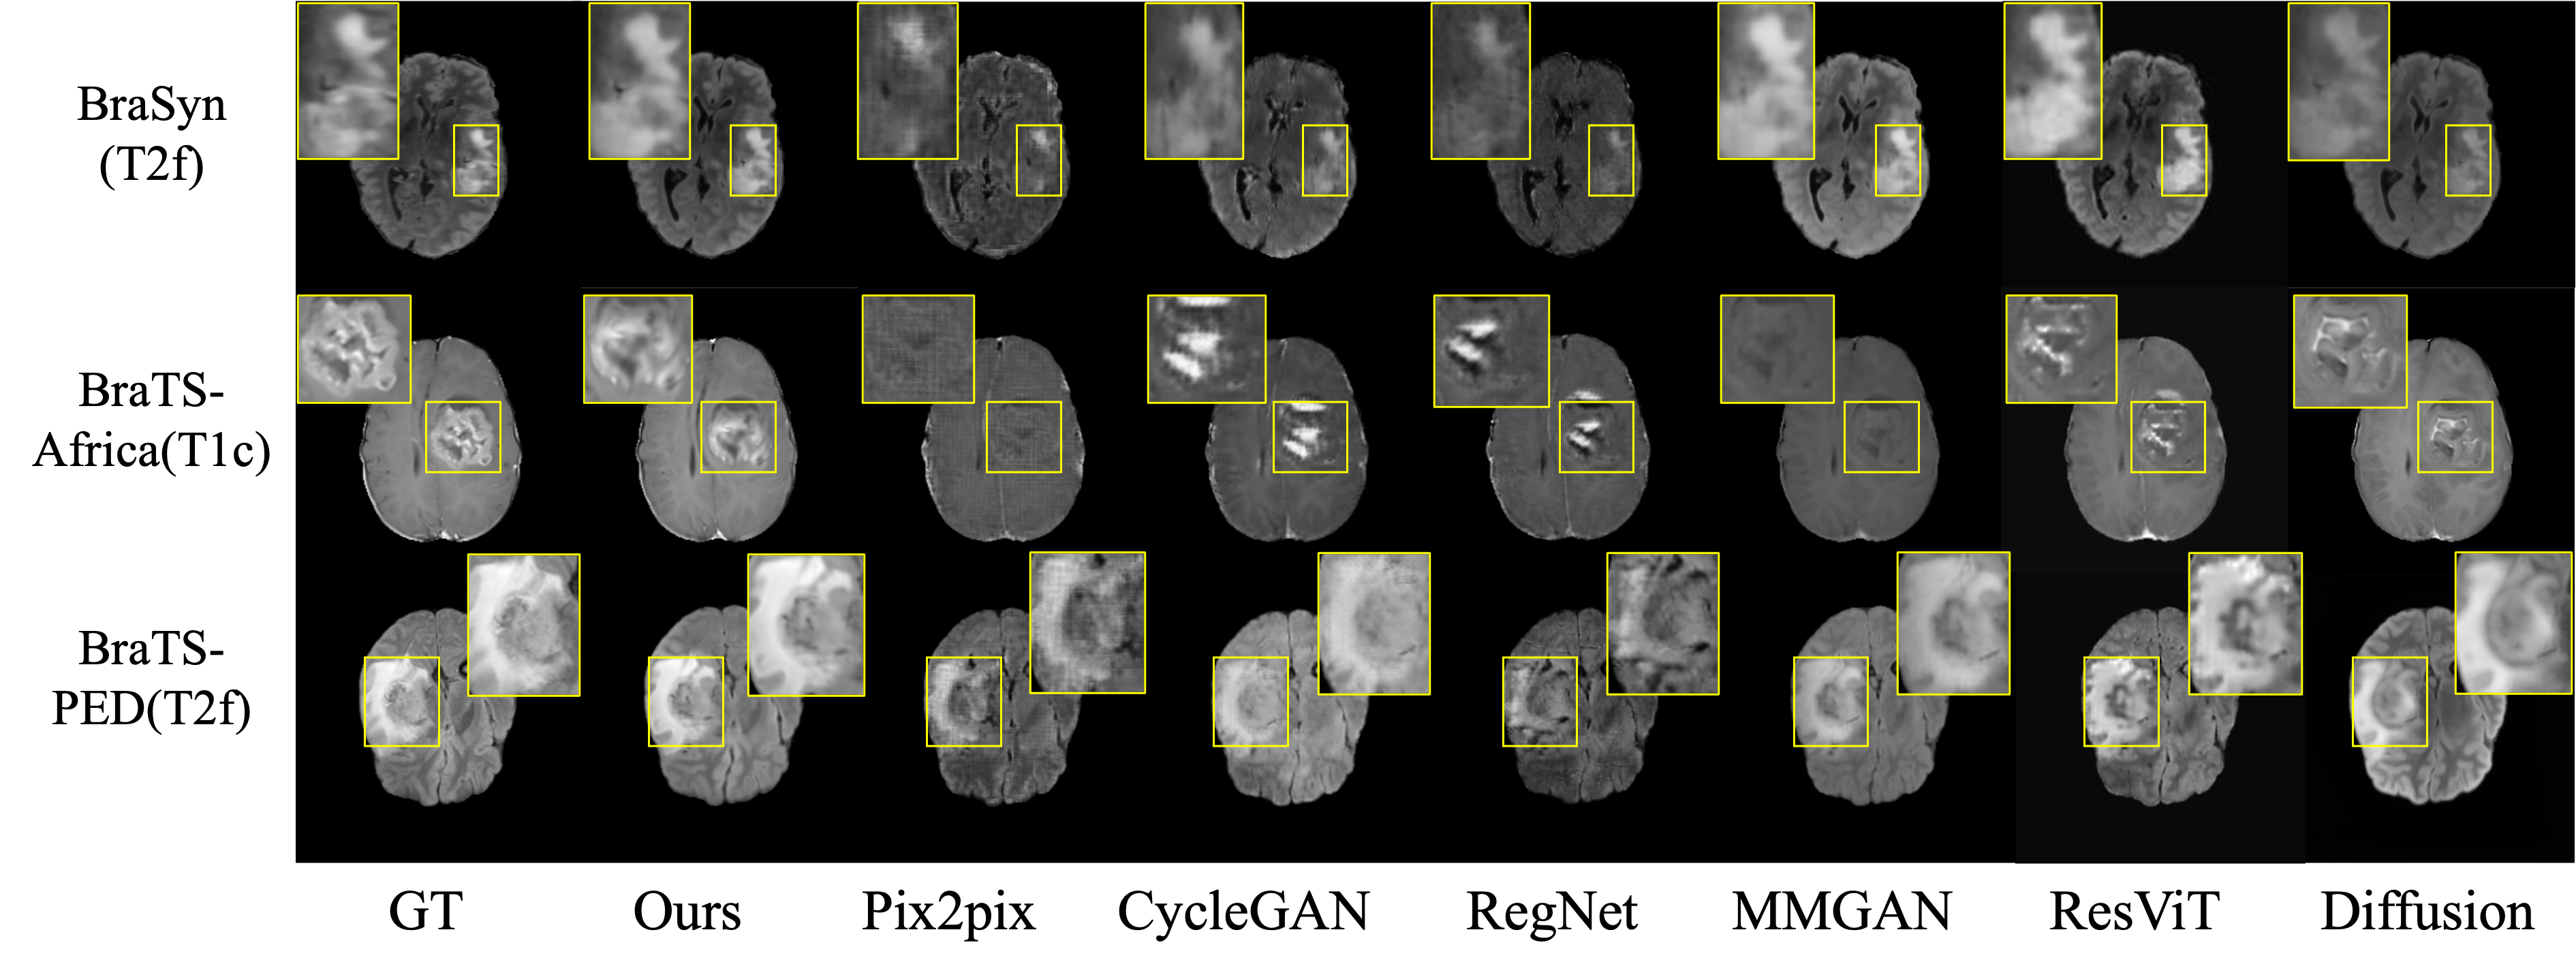

Refer to caption

Figure 3: Visual comparisons of ours and other methods.